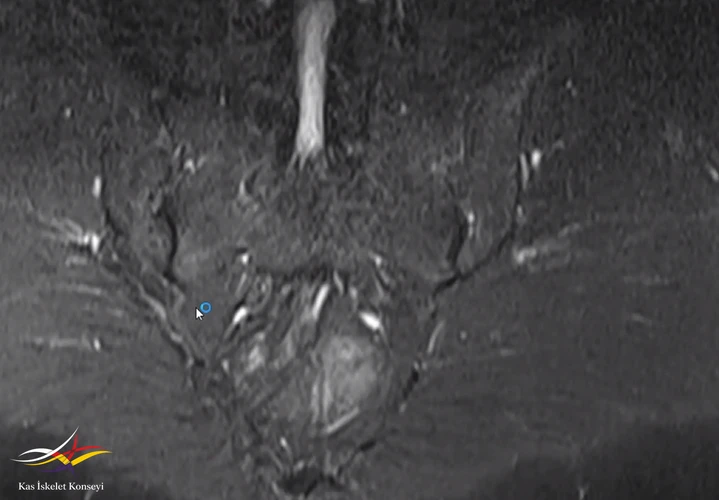

Resim 1. Sakroiliak MRG

Resim 3. Sakroilak MRG